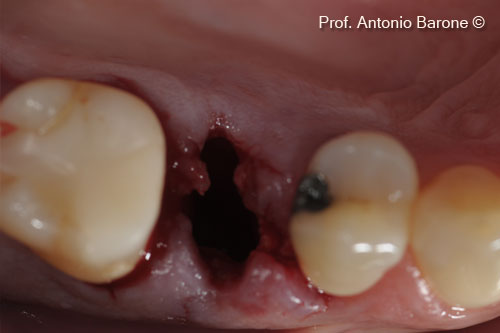

Tình hình

ban đầu

Một bệnh nhân nữ (54 tuổi) cho thấy răng bị gãy ở vị trí số 15.

Hình ảnh lâm sàng mặt nhai của một chiếc răng bị gẫy

Hình ảnh lâm sàng từ phía má của một chiếc răng bị gẫy